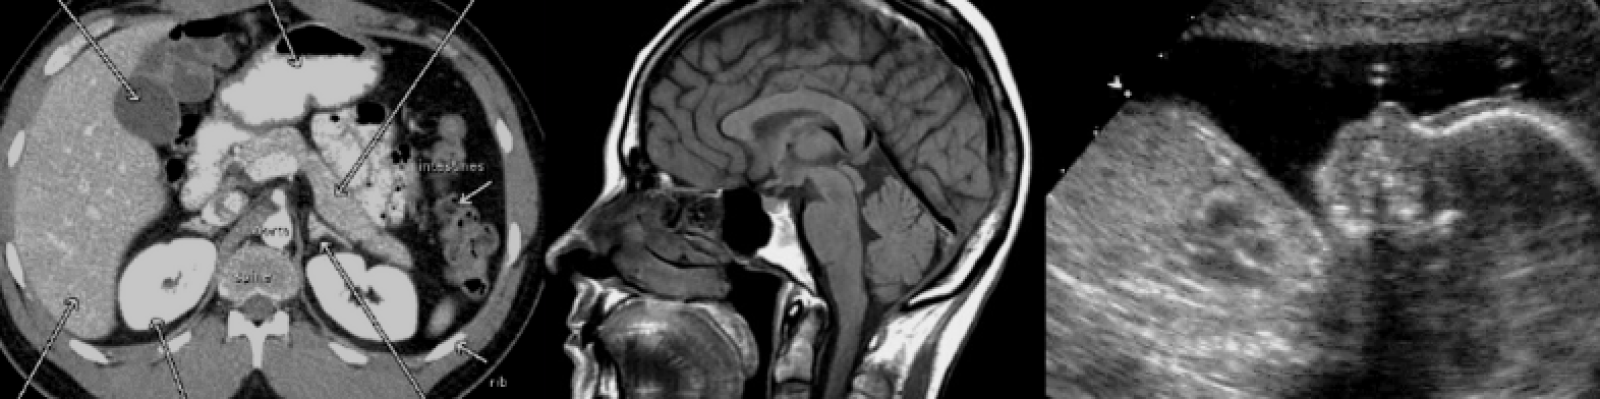

- The Computed Tomography concentration uses specialized x-ray equipment to create sectional images of the human body. Each cross-sectional image reveals complex information about body structures that are used for a variety of reasons (i.e., diagnostic, treatment planning, interventional or screening).

- The Magnetic Resonance Imaging concentration uses a powerful magnet, radio waves, and computers to create sectional images of the human body. The images reveal complex information about body structures and the chemical changes that occur as a result of the onset of disease.